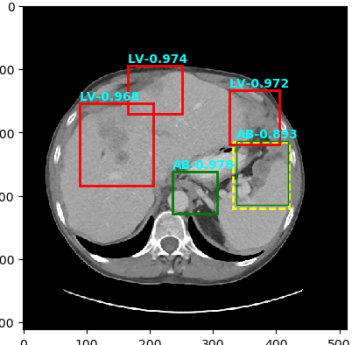

Figure 4: Six sample detection results are illustrated with the annotation lesion patches as yellow dashed boxes. The outputs from our proposed detection framework are shown in colored boxes with LiVer lesion (LV) in Red, Lung Nodule (LN) in Orange, ABdomen lesion (AB) in Green, Chest Lymph node (CL) in magenta and other MiXed lesions (MX) in blue. (a) Four lung lesions are all correctly detected; (b) Two lymph nodes in mediastinum is presented; (c) A Ground Glass Opacity (GGO) and a mass are detected in the lung; (d) An adrenal nodule; (e) Correct detections on both the small abdomen lymph node nearly aorta but also other metastases in liver and spleen; (f) Two liver metastasis are correctly detected. Three lung metastases are detected but erroneously classified as liver lesions .